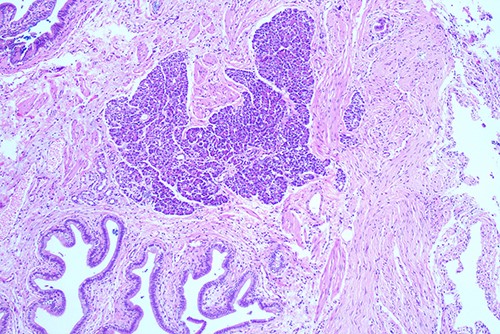

She proceeded to an elective laparoscopic cholecystectomy. At the time of her procedure, she was found to have features suggestive of chronic cholecystitis with peritoneal adhesions. Her procedure was straightforward and intraoperative cholangiogram showed a spiral cystic duct with the trifurcation of intrahepatic ducts. Her common bile duct appeared mildly dilated however tapered at the lower end and showed filling of the duodenum with no filling defects. The histology from the gallbladder showed variable fibromuscular thickening of the wall with intramural cystic Rokitansky-Aschoff sinuses, but no significant inflammation. Focal ectopic pancreatic acinar tissue (1 mm) within the gallbladder was found (Figs 1–3). There was no evidence of intestinal metaplasia, dysplasia or malignancy.

Histological examination ×100 showing ectopic tissue consisting of pancreatic acini and small ducts. No islets are seen.